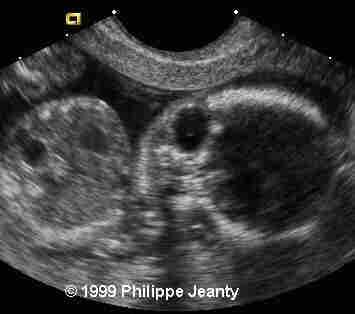

Very few, however, made the most crucial observation: the great disproportion between the head and abdomen. That disproportion is very typical of triploidy (see the lecture on aneuploidy for another example) and I know of no other conditions where such a big difference exist without a concomitant intracranial anomaly such as hydrocephaly, or teratomas… Of course, one of you will come up with a great differential diagnosis and then we will learn even more !

An enlarged eye, and mainly the disproportion between the head-abdomen size.

Teaching point: A head much greater than the abdomen is a strong sign of triploidy.

Although commonly encountered in spontaneous abortions, triploidy is rarely seen in fetuses surviving beyond mid-pregnancy. Mid-trimester sonographic findings in three triploid fetuses are described and compared with those reported in six prior cases. While sonographic characteristics are variable, common features include: 1) second trimester-onset fetal growth retardation with a reduced growth potential pattern of anthropometric growth, 2) body asymmetry with relative macrocephaly and an elevated head:abdominal circumference ratio, 3) hydrocephalus, 4) oligohydramnios, and 5) an abnormally large and/or hydropic placenta (in cases of paternal origin). Genetic amniocentesis and amniotic fluid chromosome studies should be performed when ultrasound findings suggestive of fetal triploidy are identified.